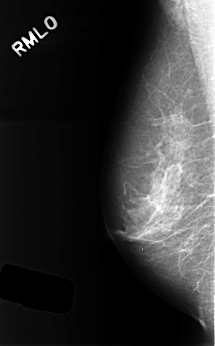

Digital Database for Screening Mammography

Volume: benign_06 Case: C-0326-1

C_0326_1.RIGHT_MLO

RIGHT_MLO LINES 4488 PIXELS_PER_LINE 2792 BITS_PER_PIXEL 12 RESOLUTION 50 NON_OVERLAY

ABNORMALITY 1

LESION_TYPE MASS SHAPE OVAL MARGINS CIRCUMSCRIBED

ASSESSMENT 3

SUBTLETY 5

PATHOLOGY BENIGN